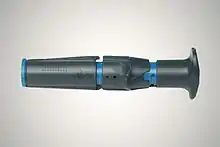

The automatic intra-osseous devices allow quick and safe access to the patient's vascular system for fluid and drug administration. There are several FDA approved IO devices, categorized by their mechanism of action:

- Power Driver: EZ-IO By Arrow Teleflex.

- Spring Loaded: BIG Bone Injection Gun and NIO

- Manual / Hand Powered : Fast 1, Fast Combat and Fast Responder, Cook IO Needle and The Janshidi 15G

There have been several studies comparing the EZ-IO and the BIG.[12][13][14] Another paper compared the EZ-IO with the Cook IO needle.[15]